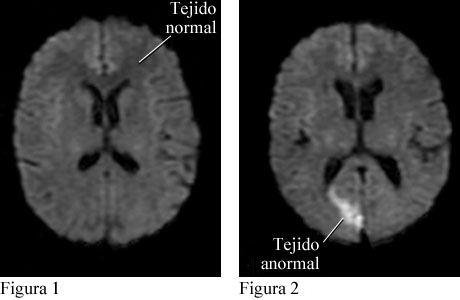

Imágenes por resonancia magnética de un ataque cerebral